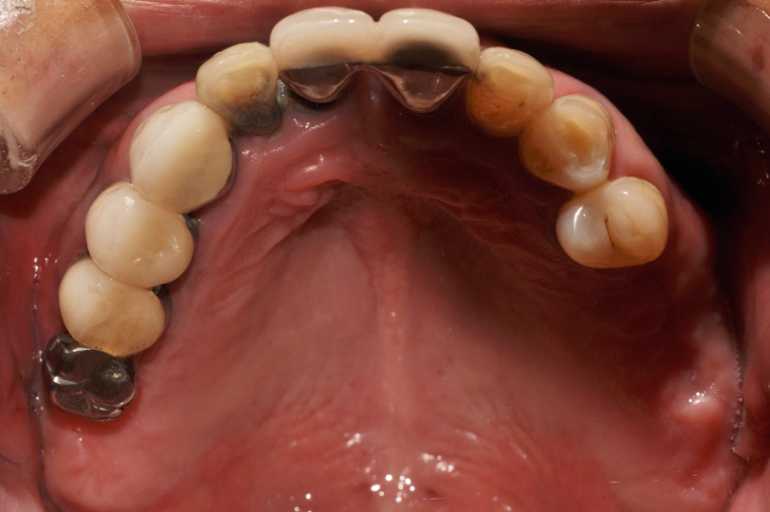

무치악 임플란트 전후 실제 사례 #3

#무치악 임플란트 환자 사례 : 기존 치아의 염증 상태로 인해 치료 시작일 때, 잔존치 전체 발치 + 상악동거상술(양쪽) + 뼈이식다수 + 임플란트 픽스처(뿌리) 17개 식립